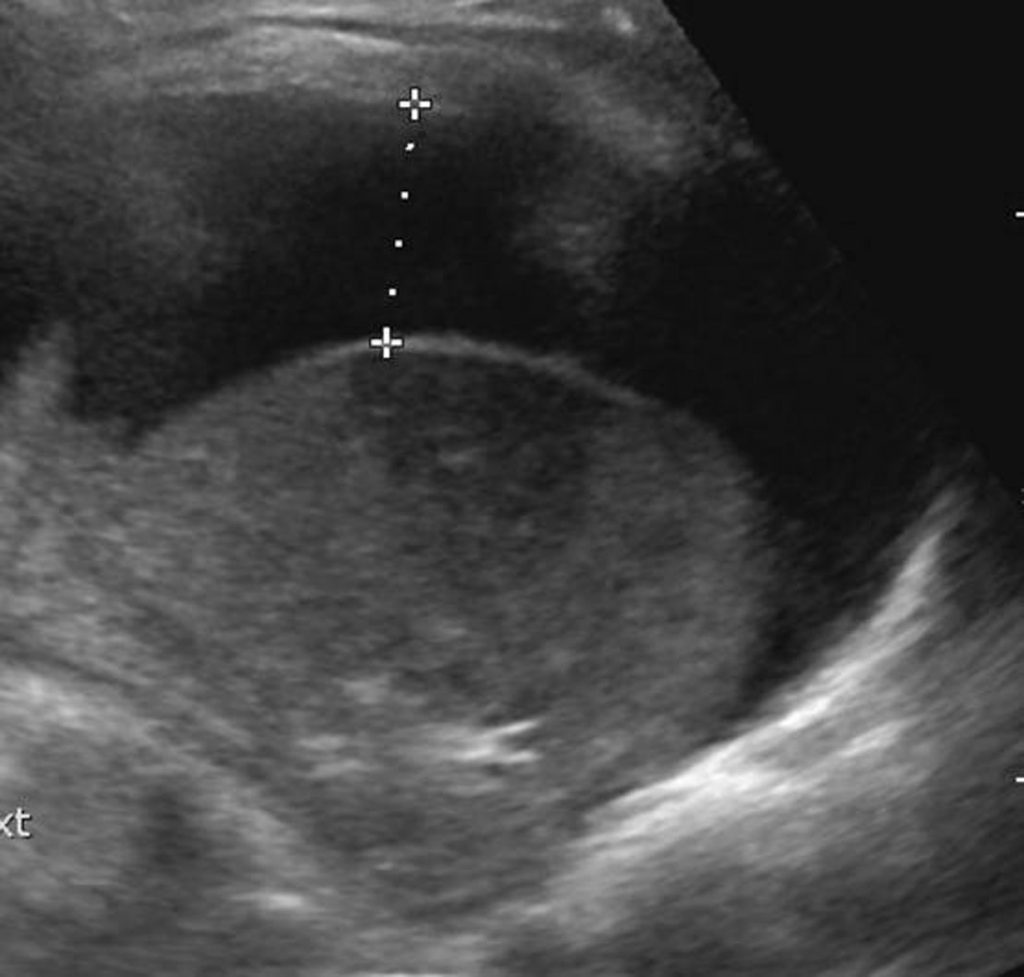

L’échographie, non irradiante, est indispensable pour identifier et quantifier un épanchement pleural liquidien, préciser l’existence de cloisons, avant d’envisager une ponction ou un drainage de celui-ci. Elle permet également de visualiser la pneumopathie si celle-ci est au contact de la paroi thoracique ou en cas d’épanchement associé (figure 126.3).

Fig. 126.3 Échographie thoracique.

Épanchement pleural liquidien, abondant, mesuré en épaisseur, ponctionnable, avec poumon condensé au contact.

Source : CERF, CNEBMN, 2022.